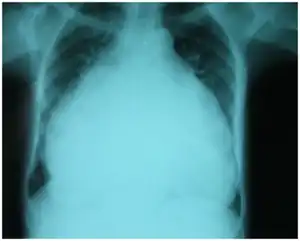

The diagnosis of TR may be suspected if the typical murmur of TR is heard. Severe TR may be suspected if right ventricular enlargement is seen on chest x-ray, and other causes of this enlargement are ruled out.

Chest-Xray: enlarged heart in TR and mitral valve disease -